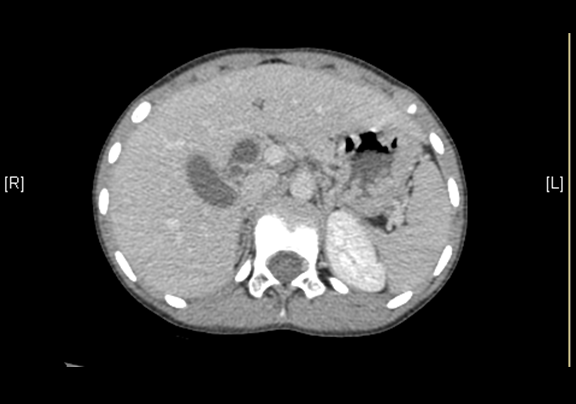

上腹部CT平扫:先天性胆管囊状扩张症并胆囊结石、胆囊炎症。

上腹部增强CT:肝总管-胆总管中上段梭形增宽,符合先天性胆管扩张所见(Ⅰ型)。

术前CT检查:

动脉期

静脉期

平衡期